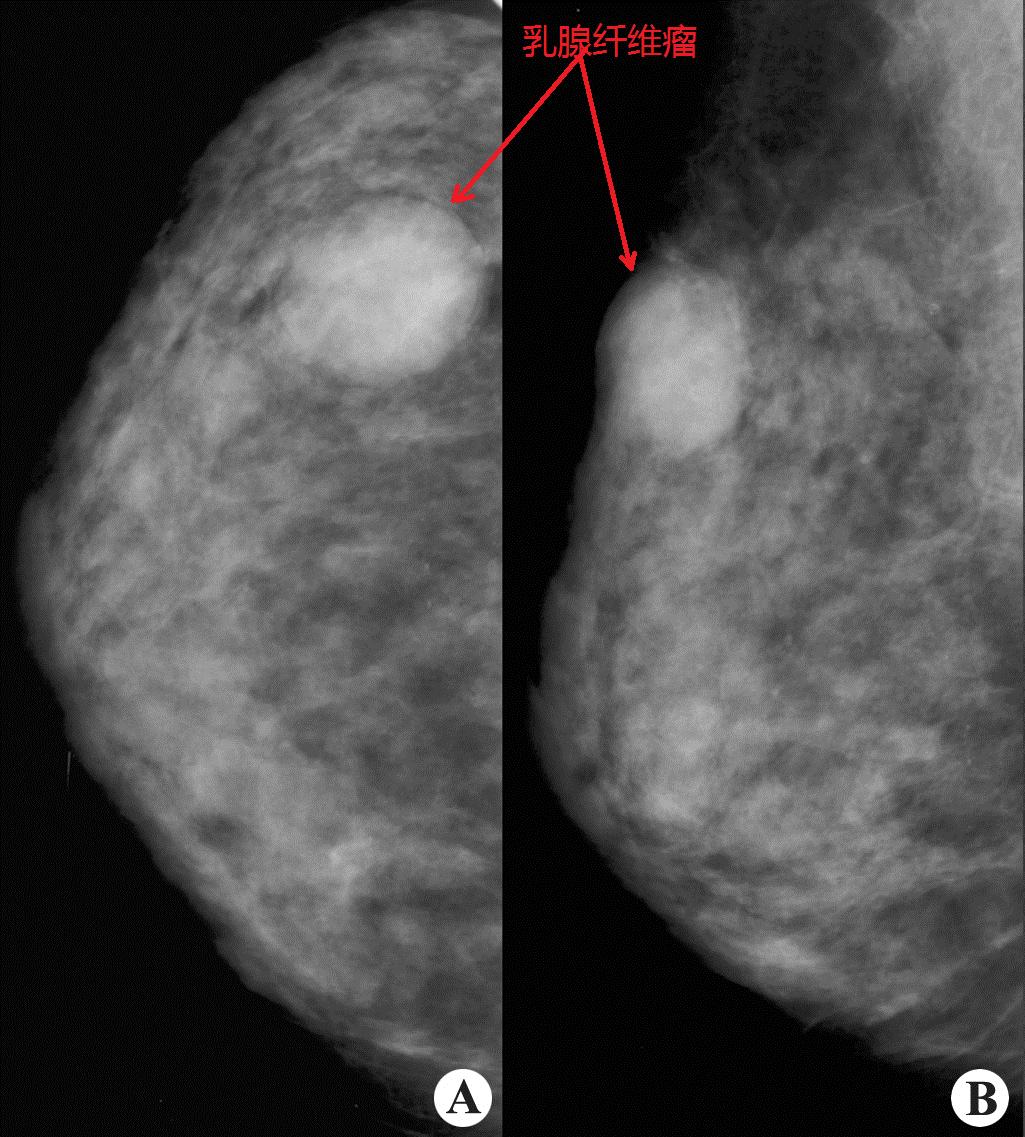

乳腺内的良性肿瘤,对生命不造成威胁

肿瘤的种类繁多,数目不一(多为一个,也可多个)、形状多样(息肉状、结节状、分叶状、囊状、溃疡状或弥漫浸润性生长)、颜色各异(一般灰白或灰红,脂肪瘤呈黄色,恶性黑色素瘤呈黑色,血管瘤呈红色或暗红色)、硬度不同(与肿瘤种类、肿瘤实质与间质的比例及有无变性、坏死有关,如脂肪瘤很软,骨瘤很硬)。

肿瘤可长在身体的不同部位,其大小和发展速度也各不相同,对健康或生命的危害也有很大的差异:有的可长期"和平共处",为“良性肿瘤”;有的则必须"除恶务尽",否则就会"遗害无穷",为“恶性肿瘤"。在良性、恶性肿瘤之间,还有“交界性肿瘤”等概念。